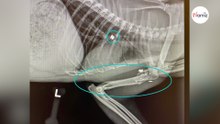

Rifugio salva un gatto gravemente ferito: le radiografie del veterinario rivelano l'impensabile

per Wamiz Italia- 2 anni fa

1 visualizzazione